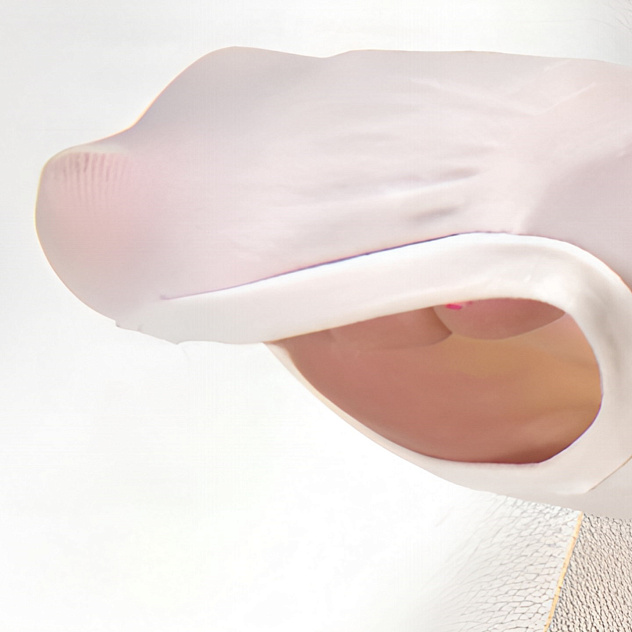

Компрессионный трикотаж бренда EVOLUTION от производителя Тривес - высокое качество сырья от немецких производителей, подтвержденный сертификатом ОЕКО-ТЕХ® STANDART 100. Пряжа ZIMMERMANN, изделие предназначено для лечения и профилактики заболевания вен.

— гипоаллергенная резинка на силиконовой основе обеспечивает надежную фиксацию изделия;

—уникальная технология вязки, обеспечивающая более высокую растяжимость трикотажа в разных направлениях, что облегчает процесс надевания и позволяет унифицировать рост, подбор размера;

—пористая вязка обеспечивает нормальный воздухообмен;